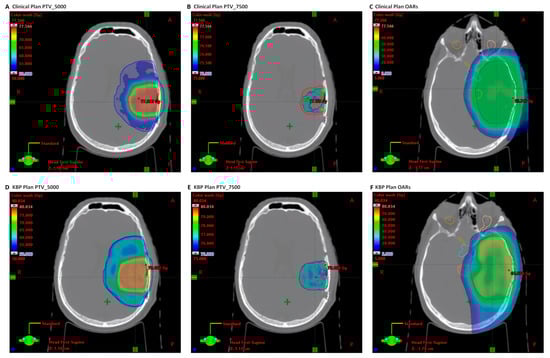

3.3. NRG-HN001 Proton Plan Quality Review